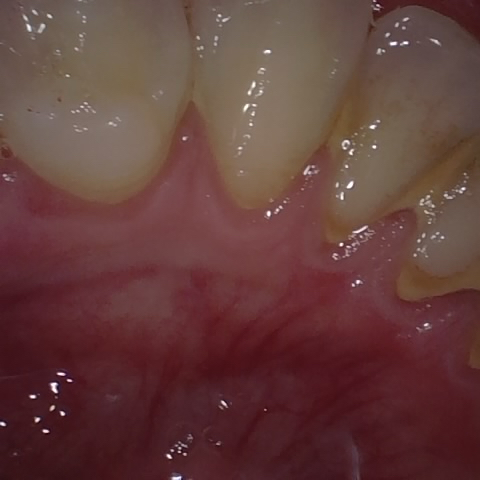

Annotated as "Good"